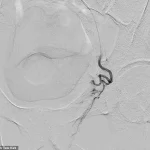

The procedure itself involves a minimally invasive technique where a catheter is guided into the arteries supplying blood to the prostate.

Pre-embolization imaging reveals the catheter’s placement within the artery feeding the left half of an enlarged prostate.

Once the embolic material is deployed, post-embolization imaging confirms the absence of blood flow to the prostate tissue from the treated artery.

This targeted approach reduces the risk of collateral damage to surrounding tissues, a critical advantage in preserving sexual function—a concern that has historically plagued other treatments.